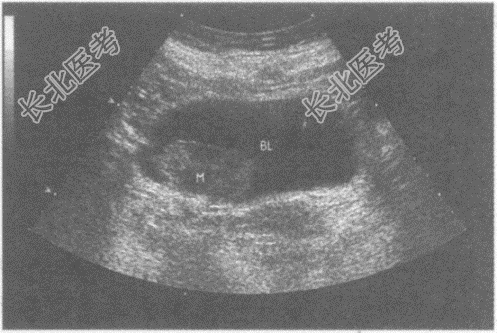

超声综合描述: 膀胱横切7:00~8: 00可见3.9cm×2.0cm中等回声,向膀胱内突起, 边界清晰,基底较宽, 内回声不均,CDFI: 内可见丰富动静脉血流信号,PW: 以动脉频谱为主。见下图及彩图。